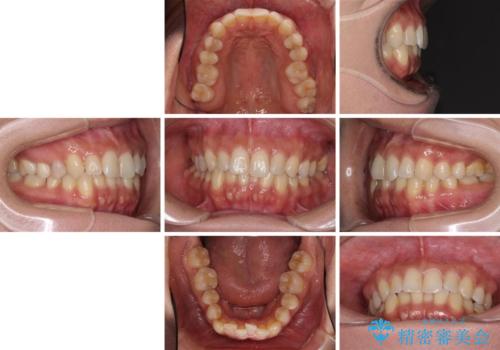

沖縄から飛行機で通院 インビザラインによる矯正治療

- 患者様

- 30代女性

- 矯正装置

- インビザライン

- 治療期間

- 3年8ヶ月

- 定期的に東京に来るので、沖縄から矯正治療で通院したいとのことで来院された患者様です。

歯列不正は軽度であったので、応急処置の少ないインビザラインにて矯正治療を行うこととしました。

通院途中に、仕事の都合で東京に来る機会が激減してしまったため、なかなか治療が進まず、当初終了予定であった時期が2年近くずれ込んでしまいました。